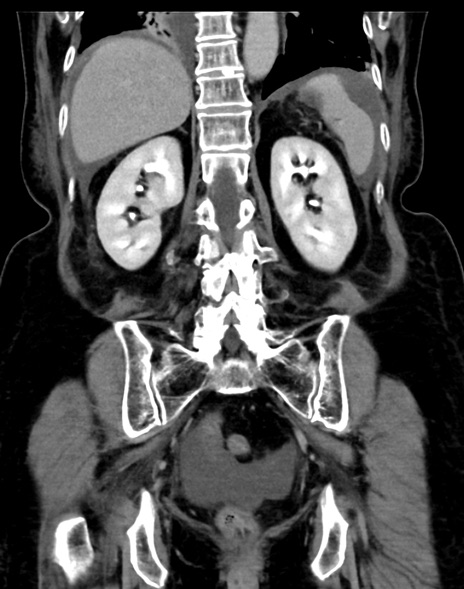

症例13 CT(冠状断像)1日半後